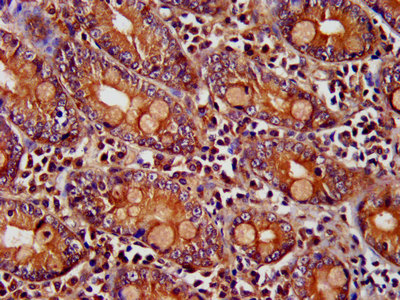

IHC image of CSB-PA868272LA01HU diluted at 1:400 and staining in paraffin-embedded human small intestine tissue performed on a Leica BondTM system. After dewaxing and hydration, antigen retrieval was mediated by high pressure in a citrate buffer (pH 6.0). Section was blocked with 10% normal goat serum 30min at RT. Then primary antibody (1% BSA) was incubated at 4°C overnight. The primary is detected by a biotinylated secondary antibody and visualized using an HRP conjugated SP system.